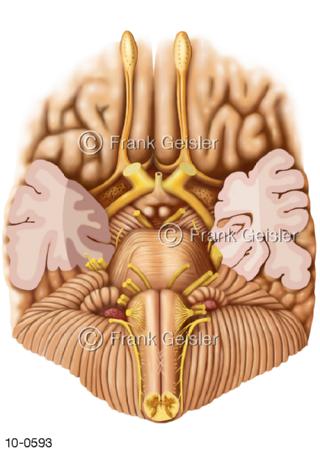

Bildergalerie Nervensystem

Bilder zum Nervensystem,dem Gehirn, Teil des zentralen Nervensystem, Zentralnervensystem ZNSmit Rückenmark, Abbildungen zum Nervengeflecht (Nervenplexus), die Verflechtungen von Nervenfasern, aus der Wirbelsäule hervortretende Nervenäst sowie Nervenzellen der Nerven